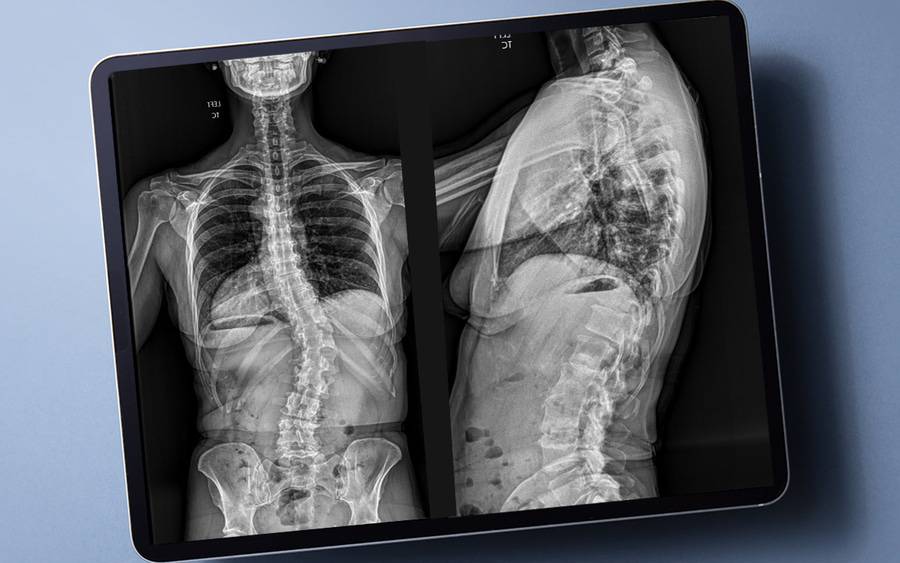

In the past, if physicians needed images of the entire spine, they’d have to take multiple X-rays, which would then have to be digitally spliced together. The patient would be repeatedly exposed to radiation to capture those images — both before and after surgery.

The EOSedge imaging system allows doctors to quickly image the entire body, from the top of the head to the bottom of the feet, with one scan. Additionally, patients simply walk into a tube-like device rather than laying down — and being moved around — on a table or standing in front of a plate.

This new method reduces patients’ radiation exposure by 80% to 90%, while providing doctors with more information than they had before, explains Robert Eastlack, MD, an orthopedic spine surgeon at Scripps Clinic Torrey Pines.

“This full-body image gives us a clear picture of all the parts of the body, and we can see how those parts are working together to impact and shape the spine,” Dr. Eastlack says.